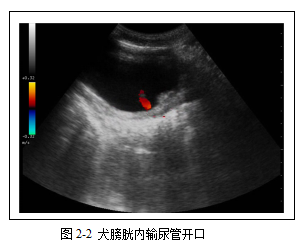

在膀胱背侧壁三角区可能见到输尿管尿液的射流。B型声像图上表现为突发的强回声斑片,彩色多普勒显示为红色脉冲流(图2-2)。输尿管射流是否明显,与膀胱内尿液与输尿管喷射的尿液比重差异有关。